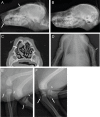

One to two percent of all children are born with a developmental disorder requiring pediatric hospital admissions. For many such syndromes, the molecular pathogenesis remains poorly characterized. Parallel developmental disorders in other species could provide complementary models for human rare diseases by uncovering new candidate genes, improving the understanding of the molecular mechanisms and opening possibilities for therapeutic trials. We performed various experiments, e.g. combined genome-wide association and next generation sequencing, to investigate the clinico-pathological features and genetic causes of three developmental syndromes in dogs, including craniomandibular osteopathy (CMO), a previously undescribed skeletal syndrome, and dental hypomineralization, for which we identified pathogenic variants in the canine SLC37A2 (truncating splicing enhancer variant), SCARF2 (truncating 2-bp deletion) and FAM20C (missense variant) genes, respectively. CMO is a clinical equivalent to an infantile cortical hyperostosis (Caffey disease), for which SLC37A2 is a new candidate gene. SLC37A2 is a poorly characterized member of a glucose-phosphate transporter family without previous disease associations. It is expressed in many tissues, including cells of the macrophage lineage, e.g. osteoclasts, and suggests a disease mechanism, in which an impaired glucose homeostasis in osteoclasts compromises their function in the developing bone, leading to hyperostosis. Mutations in SCARF2 and FAM20C have been associated with the human van den Ende-Gupta and Raine syndromes that include numerous features similar to the affected dogs. Given the growing interest in the molecular characterization and treatment of human rare diseases, our study presents three novel physiologically relevant models for further research and therapy approaches, while providing the molecular identity for the canine conditions.